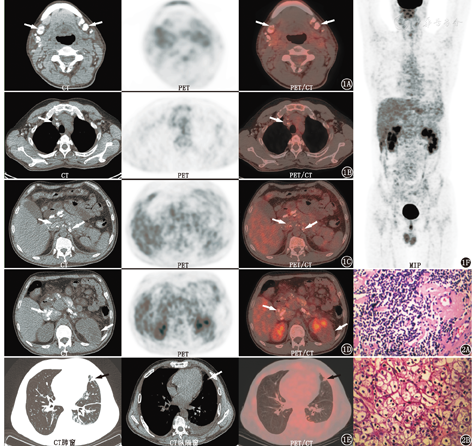

18F-脱氧葡萄糖(fluorodeoxyglucose, FDG) PET/CT(美国GE Discovery Elite 64)显像(图1)示:(1)左肾占位,代谢无明显增高;(2)双侧腮腺深部、双侧颈部、双侧锁骨上下、纵隔及双肺门、双侧腋窝、肝胃间隙、肠系膜、盆腔及双侧腹股沟区淋巴结增多,部分增大伴多发钙化,代谢无增高;(3)双肺散在少许感染,左侧胸腔积液。患者入院行抗炎治疗2周后,咳嗽咳痰症状好转,体温恢复正常。

右颈部淋巴结活组织病理检查(图2)示:淋巴结广泛玻璃样变性伴钙化,散在成熟的小淋巴细胞,小血管壁玻璃样变,未见明显淋巴滤泡结构。结合免疫组织化学及临床检查,诊断:非霍奇金B细胞淋巴瘤(惰性),符合边缘区淋巴瘤,但小淋巴细胞淋巴瘤难以完全排除。免疫组织化学检查:肿瘤细胞CD20(+),CD79α(+),B细胞特异性激活蛋白PAX-5 (+),B细胞淋巴瘤/白血病-2(B-cell lymphoma/leukemia-2,Bcl-2)蛋白(+),CD23(+),CD43(弱+),CD21[残存滤泡树突状细胞(follicular dendritic cell,FDC)网+],CD3(-),CD5(-),CD10(-),BCL-6(-),细胞周期蛋白CyclinD1 (-),Kappa (-),Lamda (-),IgG(-),IgG4(-),CD138(-),细胞增殖核抗原Ki-67标记指数:5%左右。左肾占位切除术后病理示:左肾透明细胞癌(Furhman分级:Ⅱ级)。